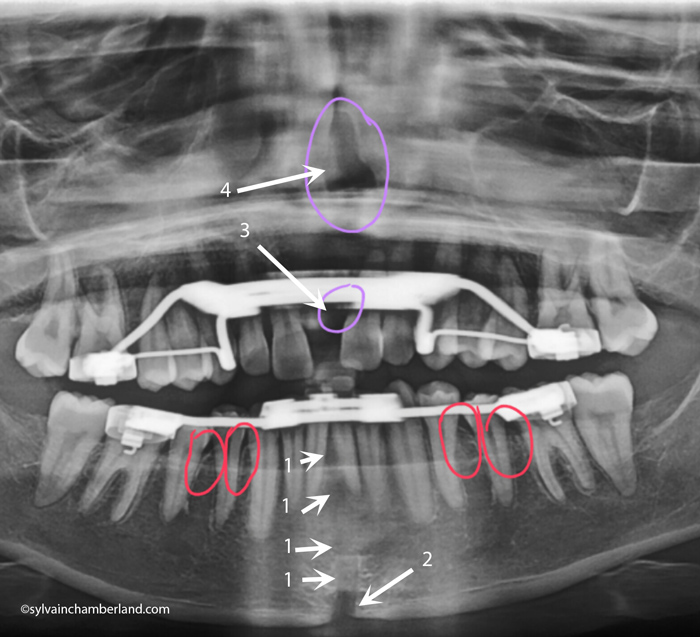

Suivi du traitement de Jennyfer

Votre chirurgie ayant eu lieu le 6 novembre 2015 et ayant terminé les activations le 1er décembre 2015, nous en sommes donc à 3 mois après l’arrêt de la distraction.

Ce délai est suffisant pour avoir une réossification des sites de distraction. Les flèches identifiées par #1 indiquent une bonne ossification du site de distraction mandibulaire et je suis agréablement surpris de voir que c’est réossifié même entre les 2 incisives inférieures. Tant mieux pour vous. La flèche #2 indique un écart au niveau du bord basilaire de la mandibule, ce n’est peut-être pas idéal, mais je crois que c’est un problème mineur, car c’est loin des dents et il est vraisemblable que le remodelage à venir va permettre un comblement.

Je n’aime pas les sites indiqués par les flèches 3 et 4. En principe, si on peut observer une réossification à la mandibule, on devrait en observer une entre les 2 incisives supérieures et au niveau du plancher palatin et au-dessus des racines des incisives. Or ce n’est pas le cas.

Cette autre photo à droite présente une guérison inachevée entre les incisives supérieures. La flèche 1 indique une possible récession de gencive entre les incisives centrales inférieures.

La flèche #2 indique une cavité au mésial de l’incisive centrale supérieure gauche qui correspond à la flèche #3 sur la radiographie panoramique. La flèche #2 sur la photo et la flèche #3 sur la radio confirme l’absence d’ossification au mésial de l’incisive. Je serais curieux de savoir s’il y a un attachement du ligament ou s’il y a une poche profonde. Je gagerais sur une poche profonde. Cela n’est pas de bon augure. Je souhaite que tout entre dans l’ordre pour vous. Il me semble évident qu’il y a eu une fracture asymétrique du septum interincisif supérieur où tout l’os est demeuré sur la dent de droite et aucun sur la dent de gauche. J’avoue craindre pour votre incisive supérieure gauche. Des soins particuliers seront nécessaires pour obtenir une guérison osseuse entre les 2 incisives.